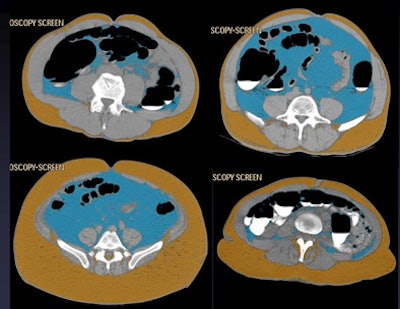

![]() |

| Four patients show different abdominal fat distribution patterns. |